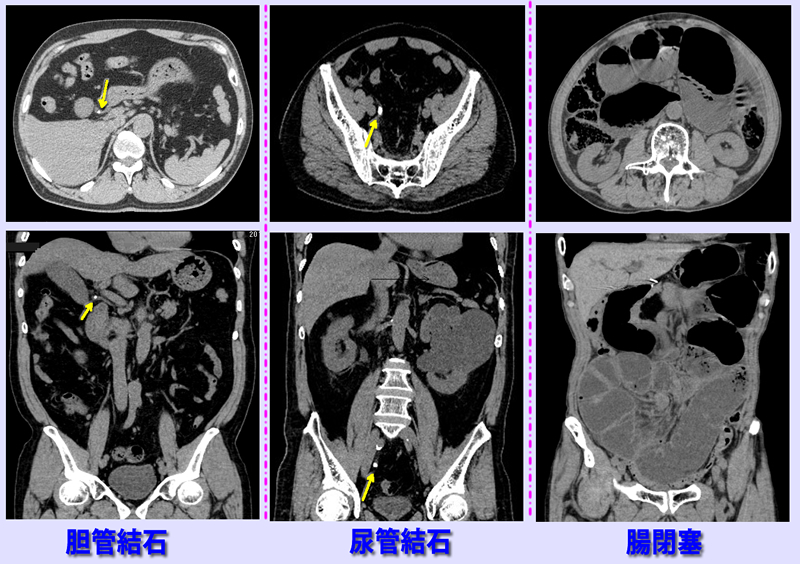

上腹部痛が持続するため夜間11時来院。左CT画像で胆管内に結石(黄色矢印)認め、胆管結石、胆管炎と診断。

中央CT画像は腹部から背部の痛み,吐き気で受診。右尿管結石(黄色矢印)と判明。

右CT画像は腹痛と嘔気で受診。腸内に多量の空気、内容物貯留認め腸閉塞と判明

急性腹部痛